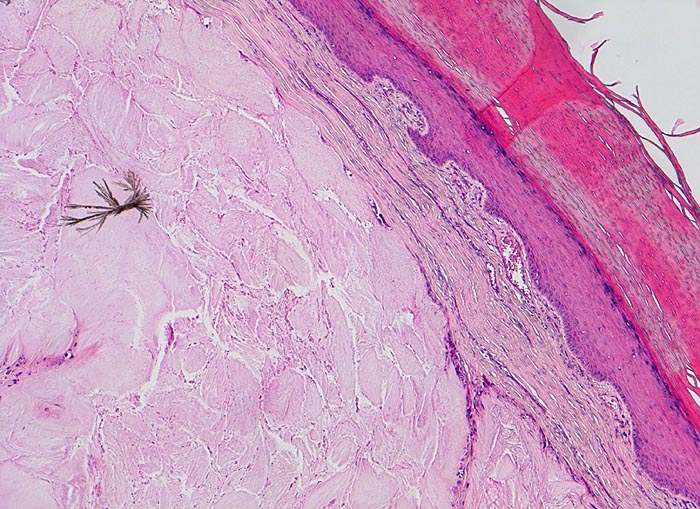

Gichttophus

Systemerkrankung/Immunpathologie

Haut

Stark verhornende Epidermis. Intradermaler Tophus bestehend aus amorphem eosinophilem Material und einzelnen bereits in der HE Färbung erkennbaren nadelförmigen Kristallen. Spärliches Entzündungsinfiltrat in der Knotenperipherie.

Rezidivierend geschwollenes und gerötetes Grosszehengrundgelenk. Schmerzattacken, teils abhängig von Nahrungs- und Getränkeeinnahme.

Histologie

50